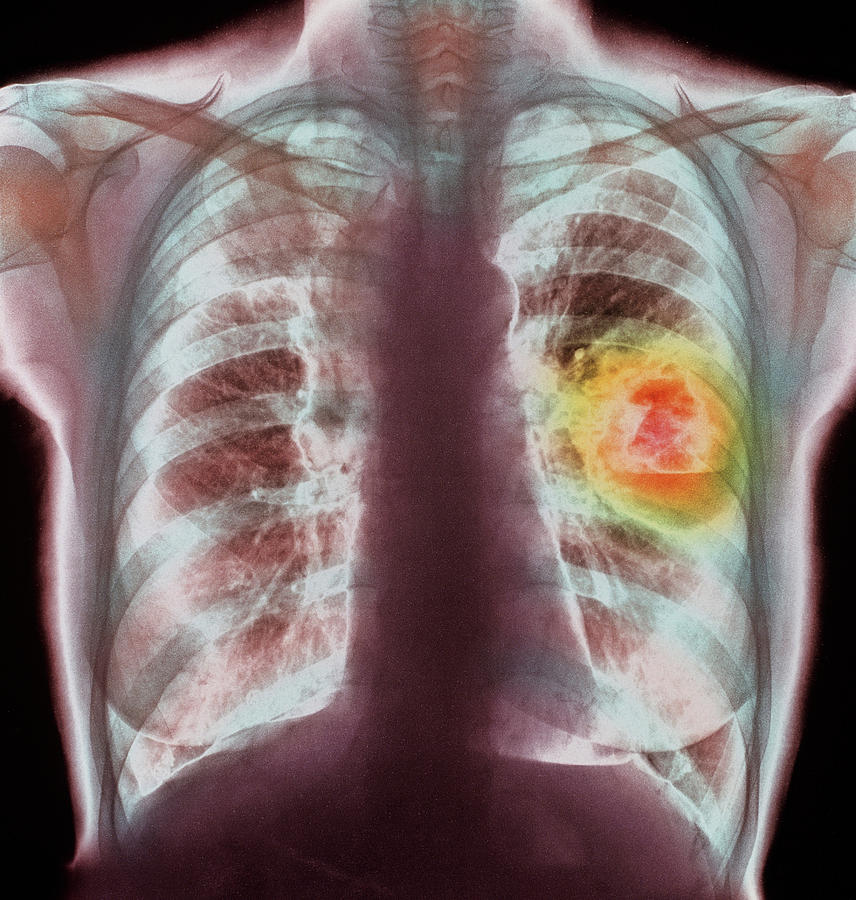

Lung Cancer Screening X Ray

Experience the clarity of Lung Cancer Screening X Ray with our curated collection of comprehensive galleries of images. featuring understated examples of photography, images, and pictures. designed to emphasize clarity and focus. Discover high-resolution Lung Cancer Screening X Ray images optimized for various applications. Suitable for various applications including web design, social media, personal projects, and digital content creation All Lung Cancer Screening X Ray images are available in high resolution with professional-grade quality, optimized for both digital and print applications, and include comprehensive metadata for easy organization and usage. Our Lung Cancer Screening X Ray gallery offers diverse visual resources to bring your ideas to life. Comprehensive tagging systems facilitate quick discovery of relevant Lung Cancer Screening X Ray content. Multiple resolution options ensure optimal performance across different platforms and applications. Time-saving browsing features help users locate ideal Lung Cancer Screening X Ray images quickly. The Lung Cancer Screening X Ray archive serves professionals, educators, and creatives across diverse industries. Instant download capabilities enable immediate access to chosen Lung Cancer Screening X Ray images. Whether for commercial projects or personal use, our Lung Cancer Screening X Ray collection delivers consistent excellence. Professional licensing options accommodate both commercial and educational usage requirements.